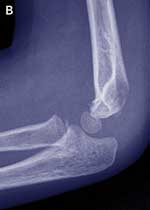

Case study — a 4-year-old girl with a painful left elbow after a fall

The parents of a 4-year-old girl bring their daughter to you after she has fallen about 1 metre from climbing equipment onto her outstretched arm. The girl is complaining of pain in her left elbow. She is unable to straighten her arm without pain and can only flex to 110°. The elbow looks swollen, mainly on the medial aspect. She has diffuse tenderness around the elbow and is unable to supinate or pronate her arm. There is no neurovascular compromise. Management

Lateral condyle fractures are inherently unstable and take a longer time to heal than supracondylar fractures. They should be managed by internal fixation in most cases. This case illustrates that it may be difficult to diagnose these fractures and that close follow-up is needed to prevent complications. |